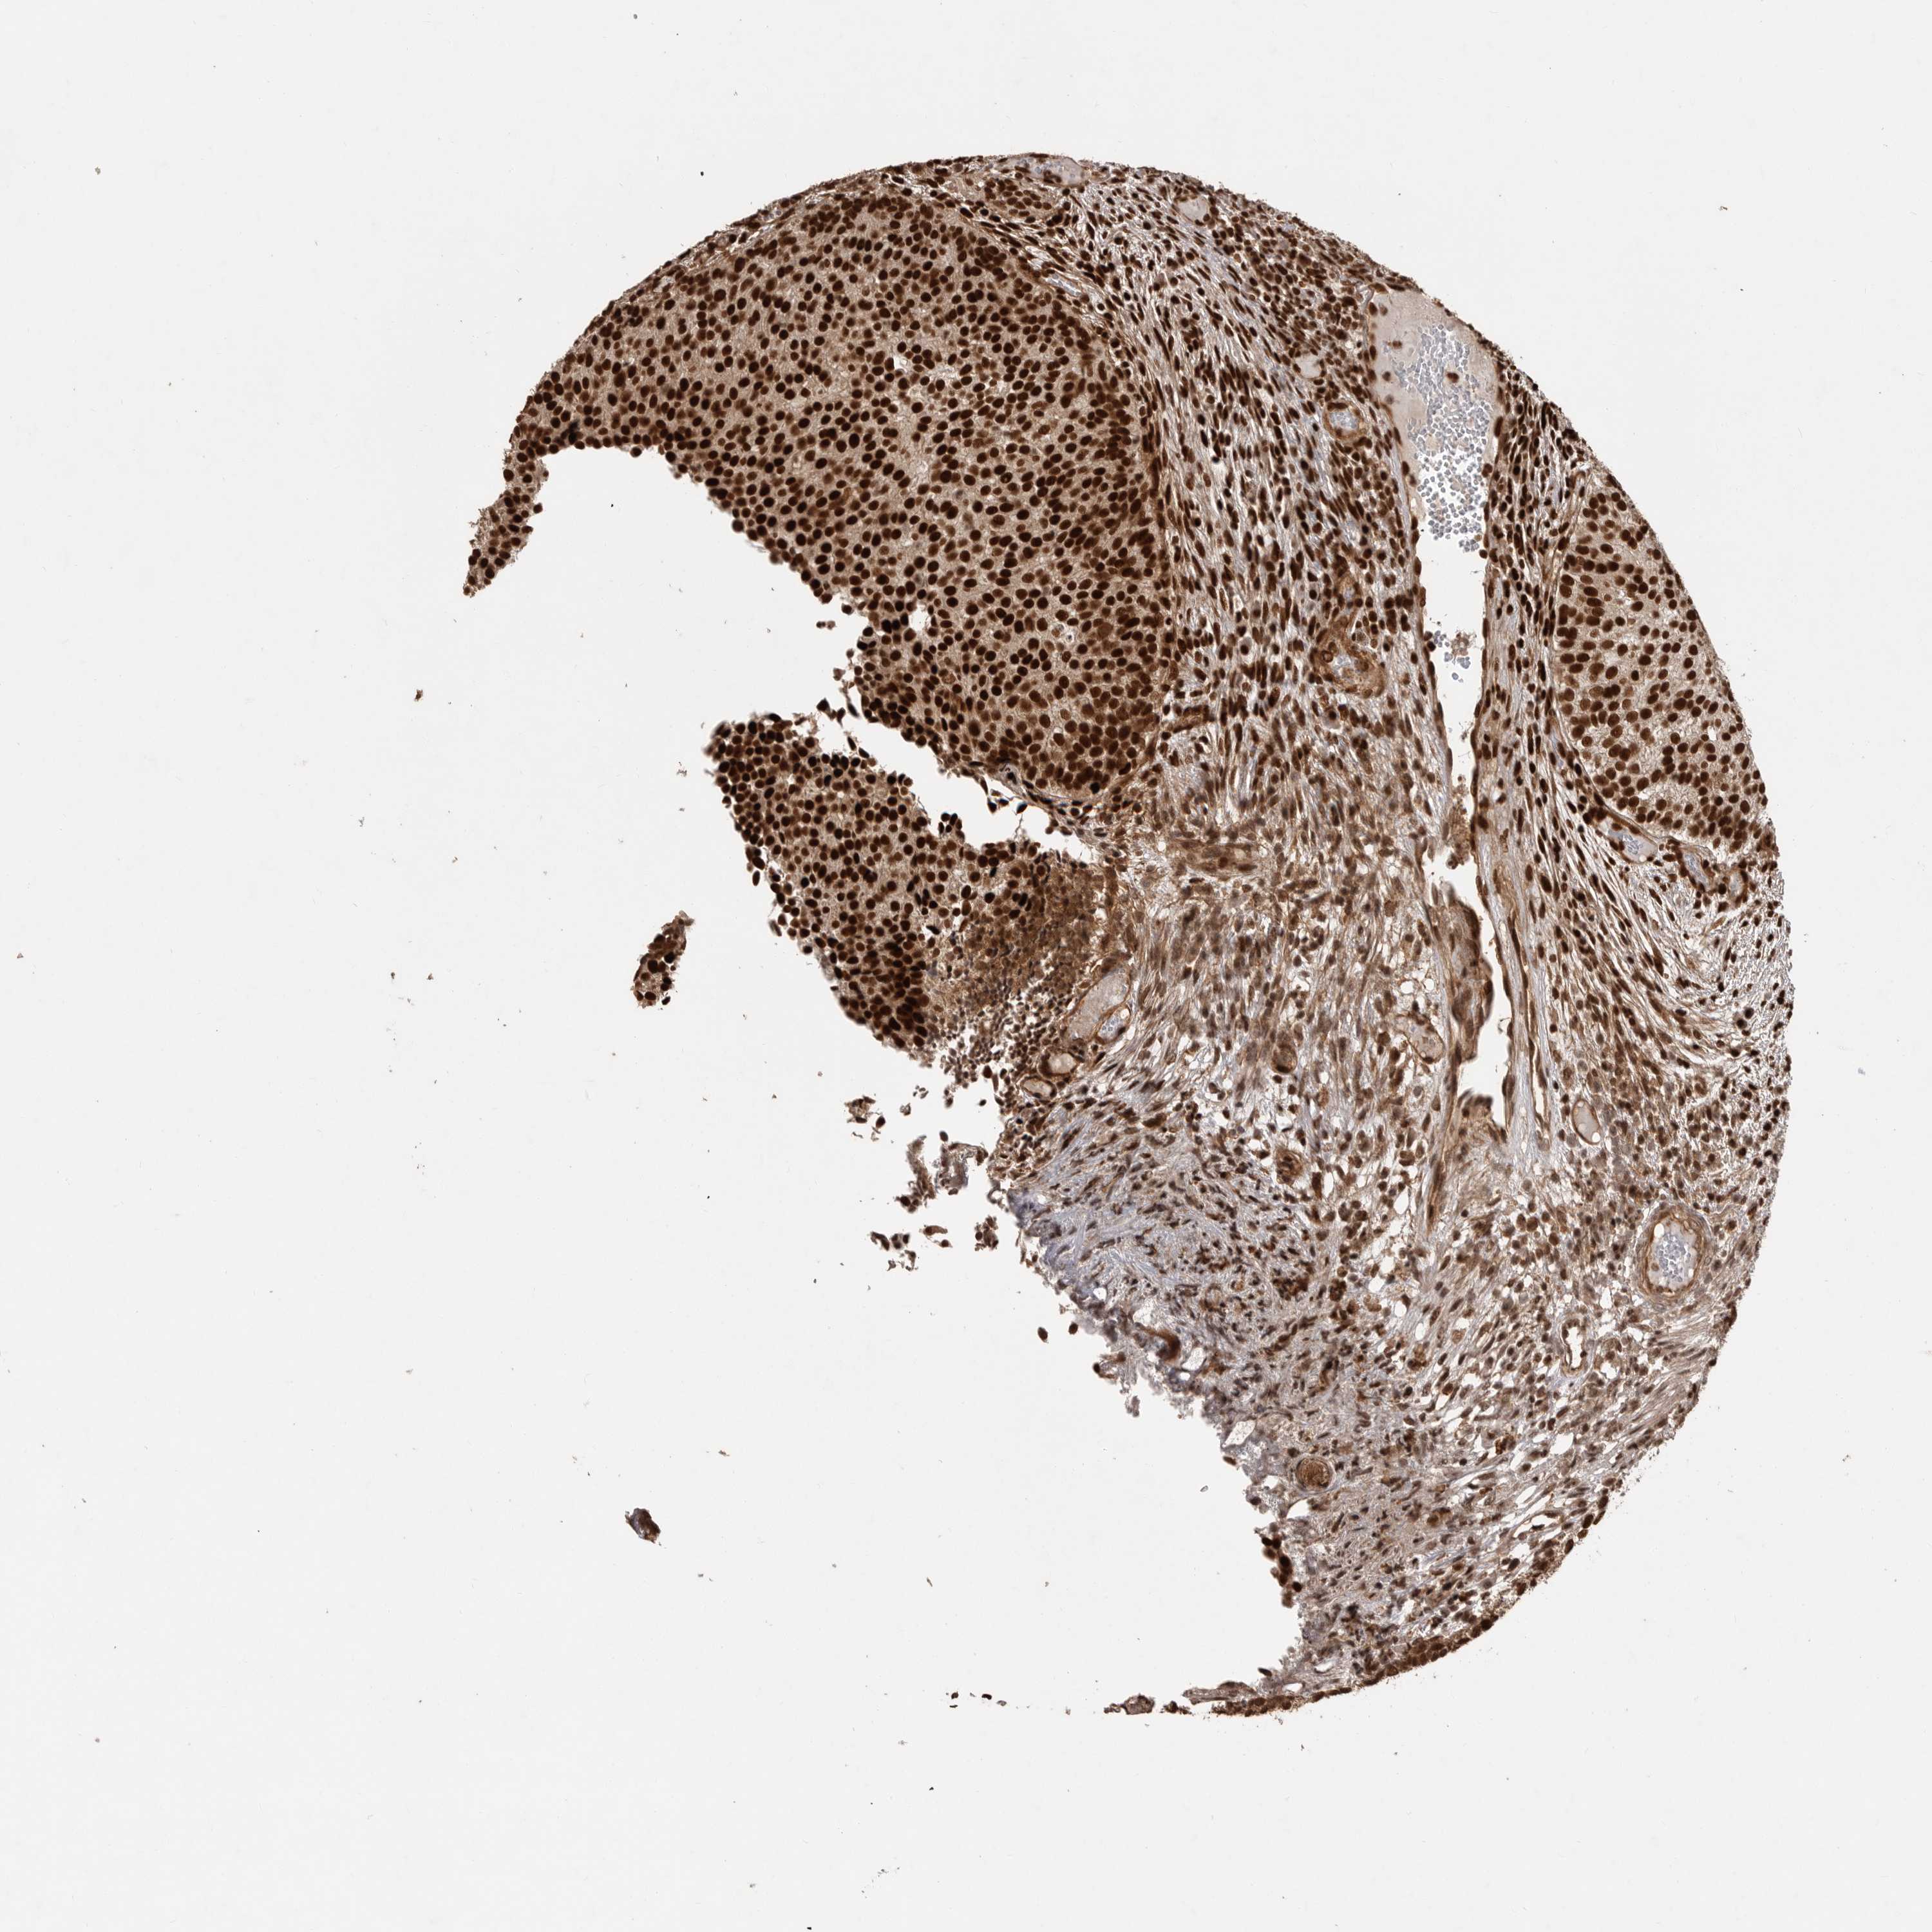

UROTHELIAL CANCER - Protein expressioni

A mouse-over function shows sample information and annotation data. Click on an image to view it in a full screen mode. Samples can be filtered based on level of antibody staining by selecting one or several of the following categories: high, medium, low and not detected. The assay and annotation is described here.

Note that samples used for immunohistochemistry by the Human Protein Atlas do not correspond to samples in the TCGA dataset.

Antibody stainingi

Antibody staining in the annotated cell types in the current human tissue is reported as not detected, low, medium, or high, based on conventional immunohistochemistry profiling in selected tissues. This score is based on the combination of the staining intensity and fraction of stained cells.

Each image is clickable and will lead to virtual microscopy that enables deeper exploration of all samples and also displays staining intensity scores, fraction scores and subcellular localization as well as patient and tissue information for each sample.

Antibody HPA027406

Antibody HPA027417

Antibody HPA027452

Staining

High

Medium

Low

Not detected

Intensity

Strong

Moderate

Weak

Negative

Quantity

>75%

75%-25%

<25%

None

Location

Nuclear

Cytoplasmic/membranous

Cytoplasmic/membranous,nuclear

Urothelial carcinoma, Low grade

Urothelial carcinoma, High grade